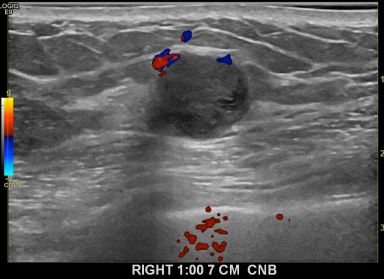

상기환자는 만져지는우측멍울로  내원하신60대후반

여성분으로 의심스러운 우측혹 조직검사 시행해 유방암 으로 진단되었습니다